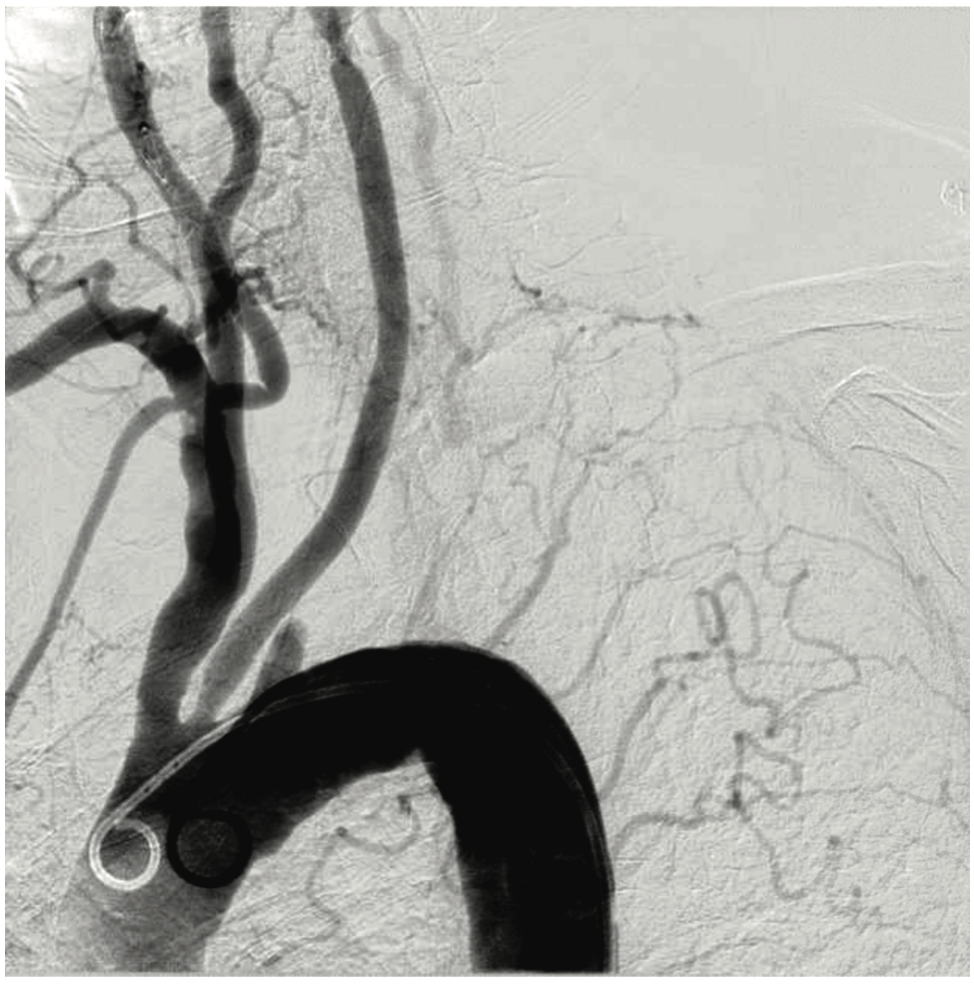

A 77-year-old female with a past medical history significant for chronic obstructive pulmonary disease, hypertension, hyperlipidemia, mild obesity, insomnia, hypothyroidism, and depression presented with progressive dizziness and increasing pain in the left arm and forearm. A peripheral angiogram revealed left subclavian stenosis diagnosed as subclavian steal syndrome (Figure 1). On the night of admission, she underwent catheterization for the removal of the clot (Figures 2-3). During the procedure, a piece of the clot embolized down to the left upper extremity. On physical examination, her skin was mottled, and no pulses were detected in the left ulnar and radial arteries. Her left-hand grip was also weak. Given these findings, she underwent another catheterization to remove a 4.0 mm clot in the left brachial artery (Figures 4-5). During the angioplasty, the brachial clot reformed despite many attempts at removal and tPA administration. Vascular surgery was consulted. As a result of the clot, the patient had developed compartment syndrome, and her cardiologist advised the family to consent to a thrombectomy and fasciotomy. During the procedure, a clot was removed from both the ulnar and radial arteries, and pressure in the forearm was relieved (Figure 6). An angiogram revealed patent radial and ulnar arteries, and flow was detected in the palmar arch (Figure 7). Upon completion of the procedure, the patient had palpable radial and ulnar pulses. The flexor muscles of the forearm were dusky but viable and responded with contraction to electrocautery.